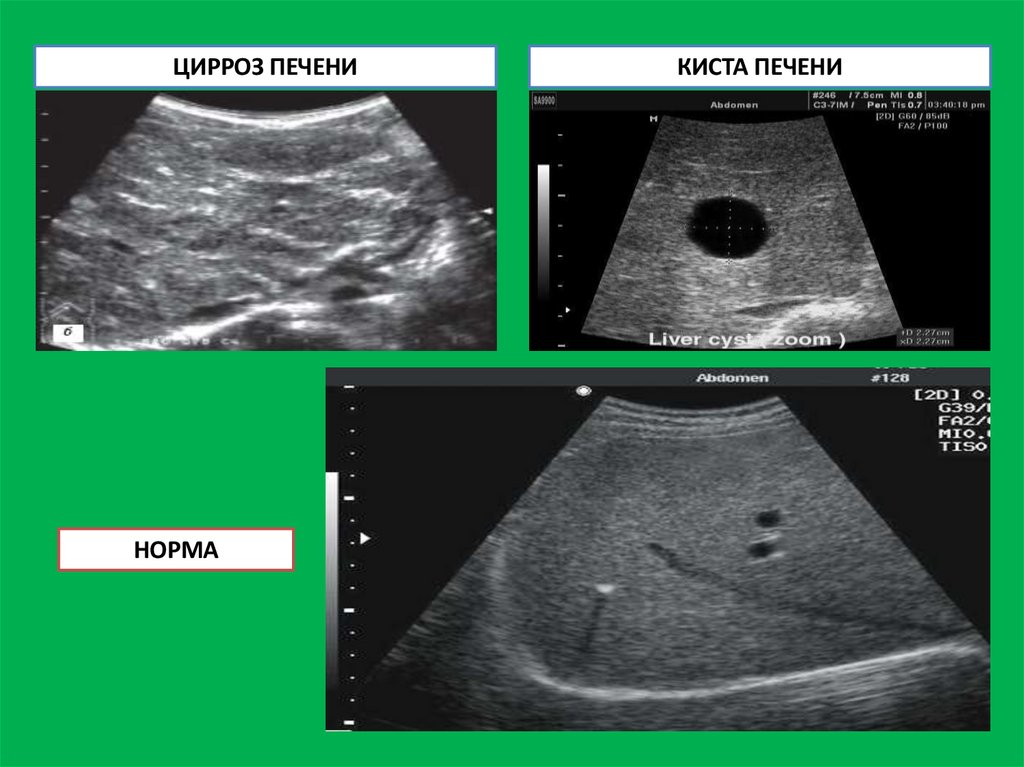

УЛЬТРАЗВУКОВЫЕ ИЗМЕНЕНИЯ ПРИ ПАТОЛОГИИ ПЕЧЕНИ

1. Цирроз печени проявляется следующими характеристиками:

Структура печени неоднородная, края бугристые.

Повышение эхогенности тканей печени (уплотнение тканей печени)

Увеличение или уменьшение размеров долей печени (зависит от

длительности протекания цирроза).

Наличие в тканях печени узлов регенерации

Увеличение диаметра портальной вены.

Увеличение размеров селезенки.

2. Хронический гепатит - проявляется повышением плотности (эхогенности)

тканей печени, увеличением ее размеров, обнаружением в тканях печени

избыточного роста соединительной ткани.

3. Доброкачественные опухоли печени определяются как очаг уплотненной

ткани, отграниченный от нормальной ткани печени.

4. Гемангиома выглядит как хорошо отграниченное от окружающей ткани

образование, заполненное жидкостью.

5. Злокачественные новообразования в печени определяются на УЗИ в виде

одного или нескольких очагов уплотненной ткани и требуют дополнительных

методов исследования с целью уточнения диагноза.

6. Абсцессы, паразиты и кисты печени представляют собой округлые,

ограниченные участки измененной ткани печени, которые содержат

жидкость.

51.

ЦИРРОЗ ПЕЧЕНИ

НОРМА

КИСТА ПЕЧЕНИ